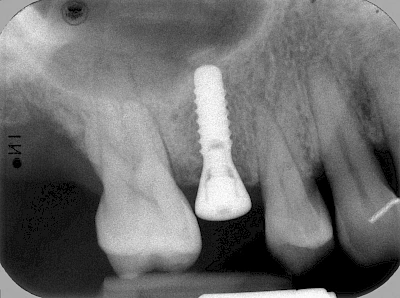

Implantate sind künstliche Zahnwurzeln. Nach einer gewissen Einheilzeit im Knochen (meist 3-6 Monate) erfolgt über einen separaten Aufbau (Abutment) die Befestigung einer Krone bzw. Brücke oder Zahnprothese.

In seltenen Fällen sind Implantate samt Aufbau aus einem Stück gefertigt. Auch gibt es Situationen, die ein Früh- oder sogar eine Sofortbelastung erlauben – dann kann die Einheilzeit der Implantate in den Knochen verkürzt oder sogar gänzlich darauf verzichtet werden.